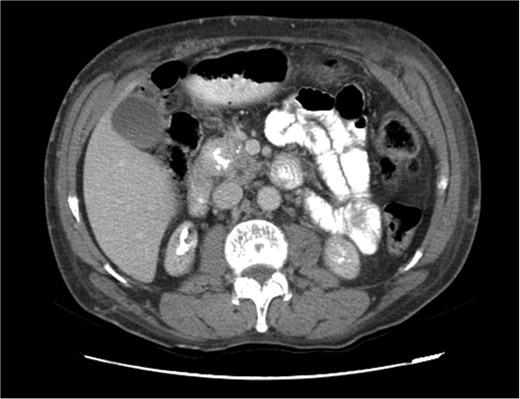

Upon admission in January 2025, the patient presented with altered mental status, dehydration, and hypoglycemia. The recurrence of hypoglycemic episodes was confirmed by laboratory studies and imaging, which identified a well-defined 3 cm mass in the pancreatic head on triphasic computed tomography (Figs 1–3). Given the diagnosis of recurrent malignant insulinoma and the possibility of resection, a surgical approach was chosen.

Triphasic computed tomography of the pancreas, arterial phase, showing a tumor in the head of the pancreas.

Triphasic computed tomography of the pancreas, late phase, showing a tumor in the head of the pancreas.

Triphasic computed tomography of the pancreas, portal phase, showing a tumor in the head of the pancreas.